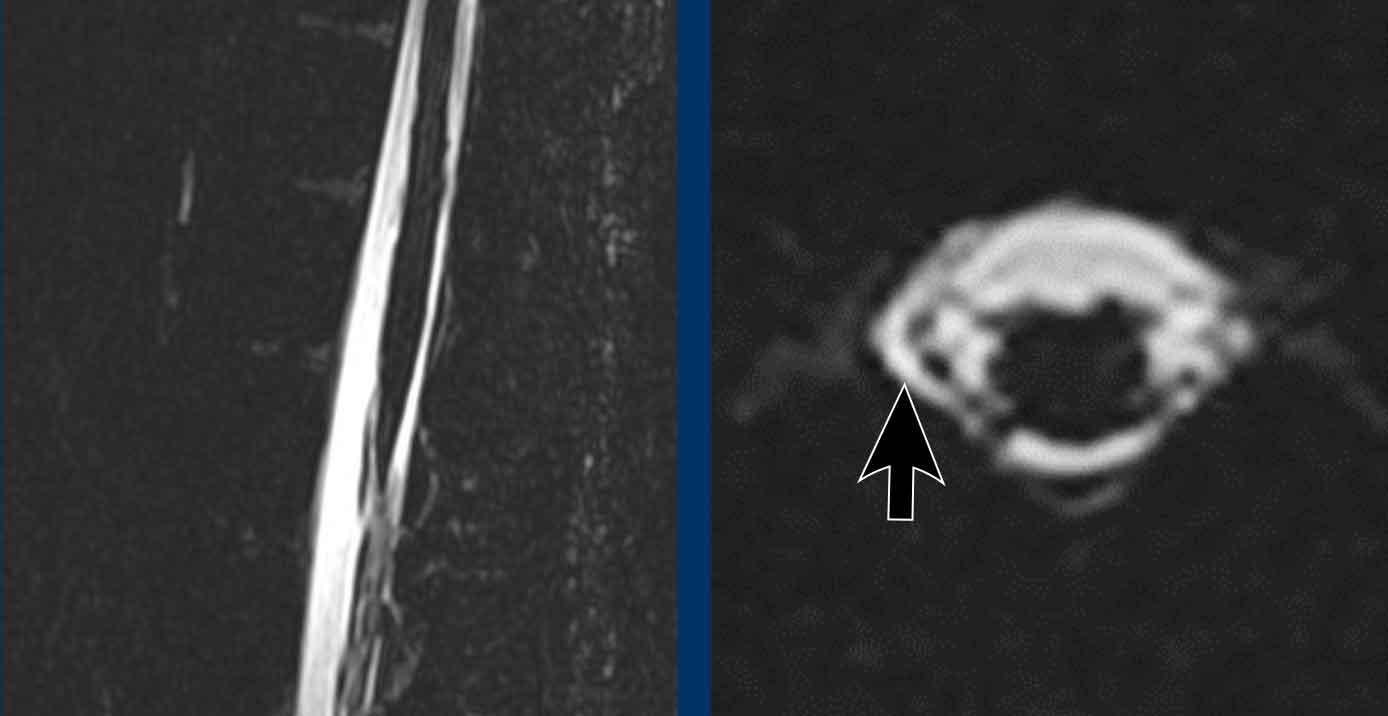

Hình ảnh

Hình ảnh cột sống không ghi nhận ổ dịch ngoài màng cứng dọc trục.

Tuy nhiên, tại mức L1 có ghi nhận sự bất đối xứng nhẹ (mũi tên).

Hình ảnh này nghi ngờ một ổ dịch ngoài màng cứng bên nhỏ ở phía bên phải.

Tiếp tục với chụp tủy đồ cột sống động…

Trên hình ảnh chụp tủy đồ cột sống động, ghi nhận hiện tượng rò rỉ thuốc cản quang ở phía bên phải từ một túi thừa bên.

Tiếp tục với hình ảnh trong phẫu thuật…

Trong quá trình phẫu thuật cột sống, một khiếm khuyết nhỏ được ghi nhận (mũi tên đen).

Màng cứng bình thường được chỉ bằng mũi tên trắng.

Khiếm khuyết đã được đóng lại.

Sau khi đóng khiếm khuyết, bệnh nhân không còn bị đau đầu nữa.

Tuy nhiên, chức năng nhận thức phục hồi về bình thường mất một thời gian dài.